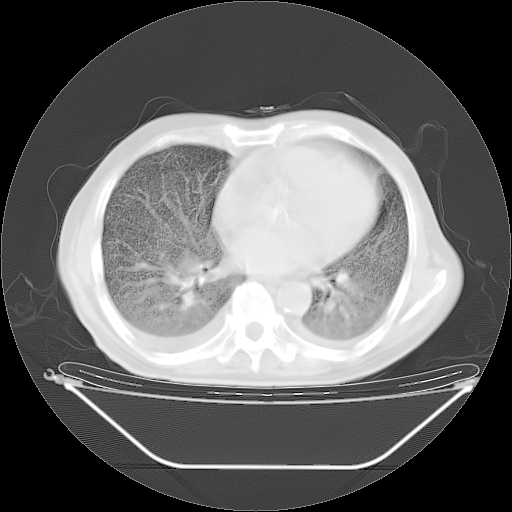

今天复查肺部CT,发现双肺广泛磨玻璃样改变。所以我把3月19日和5月9日相隔50天的肺部CT上传。请大家会诊。

2009年3月19日肺部CT片。

2009年3月19日肺部CT

大致读了系列胸部CT:纵隔窗无明显异常,肺窗:从4、27至今:主要是双肺中下野外带可见毛玻璃样改变,目前处于急性肺泡炎阶段,至于原因考虑1、结替组织或胶原血管性疾病所致?2、恶性疾病如恶组在肺部所致的表现或细支气管肺泡癌?3、药物或其它原因如肺蛋白沉着症所致肺泡炎目前不太可能?总之,明天就去请我院的呼吸科、感染科、血液科和临免专家会诊哈。